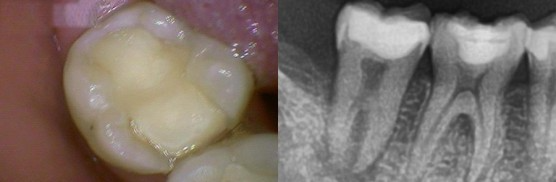

[2020.01.02 첫 내원 시 구강 상태]

아래어금니가 씹을 때 아파서 내원하셨습니다.

입안을 살펴보니 기존 수복되어있는 치아에 틈이 생겨 치수염이 생기고,

뿌리끝 부분만이 아니라 주변까지 다 염증에 이환되어있는 상태였습니다.

[치아뿌리 주변까지 염증에 이환된 상태]

치아 자체가 흔들리기도 하였고, 발치 가능성을 고지한뒤 신경치료를 시작합니다.